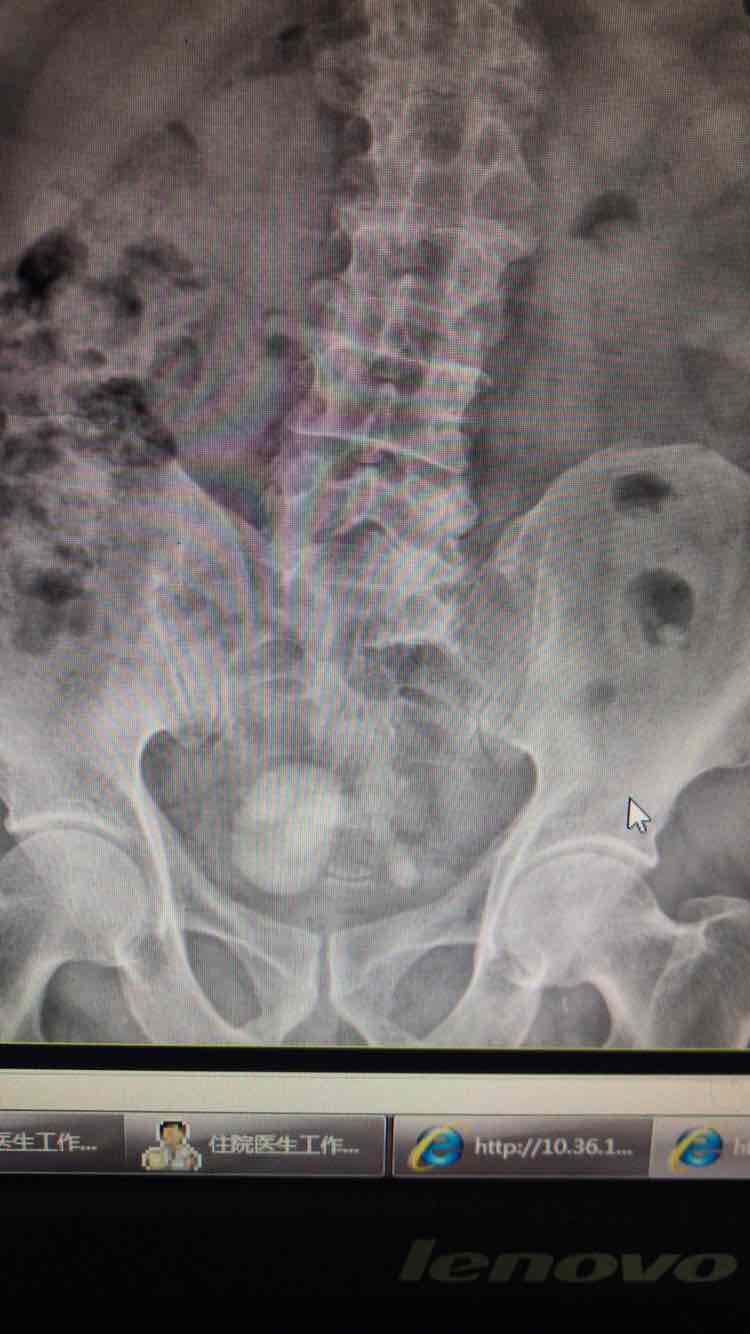

患者因尿频,尿急伴排尿困难入院,入院前外院彩超提示双肾重度积水伴双侧输尿管扩张迂曲,膀胱多发结石输尿管下段显示不清

反复阅读ct均提示输尿管全程均匀,双肾重度积水,双侧输尿管结石,

双侧输尿管末端结石,膀胱多发结石

术中膀胱镜下未见输尿管开口,右侧见膀胱憩室一样的空腔,内见结石,结石跟术前阅片一致,术中处理膀胱结石。术后拟行双肾造瘘,术后结石未见,双肾积水明显减少,再来考虑原来双肾对称性重度积水为下尿路梗阻引起